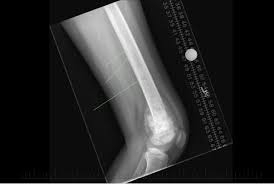

بتر الجزء الم صاب وذلك اعتمادا على حجم الورم وموقعه وقد يضطر الأطفال الم صابين بسرطان. يؤثر سرطان العظام بدرجة أكبر على العظام الطويلة في الذراعين والساقين. بشكل عام تحصل معظم حالات الإصابة بسرطان العظم عند الأطفال أو الم راهقين من هم أقل من 20 عاما.

هذه السرطانات تصيب الأطفال أكثر من الكبار. ويصيب سرطان العظام 5 في المئة المراهقين اكثر من غيرهم ومن اعراضه الام في العظام في منطقة معينة او تورم وتنخفض الحركة عند الاطفال في مكان الورم r n. العوامل التي قد تزيد من فرصة الإصابة بسرطان العظم.